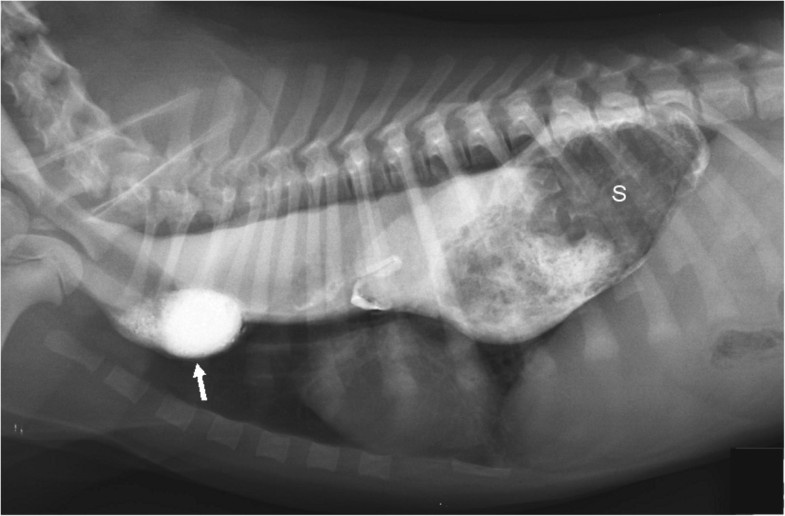

From bmcvetres.biomedcentral.com

Acute gastroesophageal intussusception in a juvenile Australian shepherd dog endoscopic Lead Exposure Dogs signs of lead poisoning in dogs include behavior changes (lethargy, aggression, constant snapping, seizures, hysteria, hiding. testing for lead poisoning in dogs is essential to detect the presence of lead in their system and to determine the appropriate treatment. lead poisoning, known as plumbism, is toxicity due to ingestion or inhalation of heavy metal lead. Young animals,. Lead Exposure Dogs.